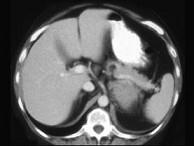

问题 女,47岁,满月脸、向心性肥胖伴高血压1个月,请结合所提供图像,作出诊断()

选项 A.左肾上腺腺瘤 B.左肾上腺腺癌 C.左肾上腺转移瘤 D.左肾上腺嗜铬细胞瘤 E.左肾上腺增生

答案 B